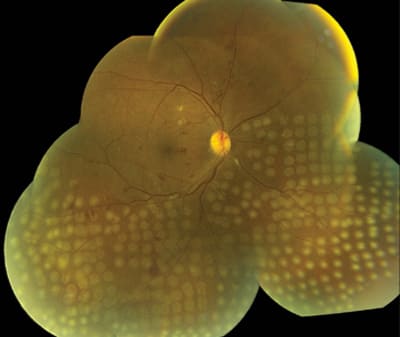

There is increased awareness among primary care providers that earlier ophthalmic examinations, better follow-up, and improved patient education all have an impact on disease progression. The greater medical community is also aware that photocoagulation is effective in the treatment of both diabetic macular edema11 and proliferative diabetic retinopathy12 (Figure 1). Pars plana vitrectomy is effective at treating vitreous hemorrhage13 and traction retinal detachment14 in many patients (Figure 2). Multiple pharmacologic therapies are being investigated as treatments for DR.15

Figure 1. Fresh panretinal photocoagulation.